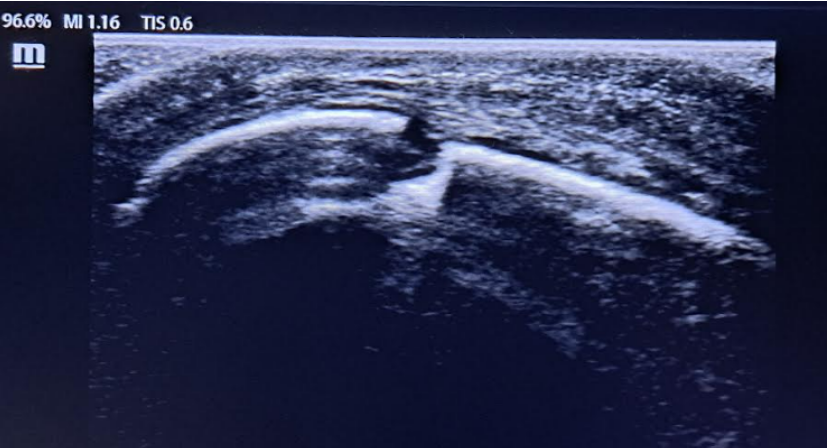

Fractura longitudinal de rótula derecha.

Si bien su diagnóstico suele ser radiológico, la ecografía musculoesquelética puede ser útil para evaluar las estructuras extensoras de la rodilla y detectar fracturas rotulianas evidenciándose una disrupción de la interfaz continua y brillante (hiperecoica) correspondiente a la cortical del hueso.

Estudios prospectivos preliminares sugieren que la ecografía musculoesquelética tiene una sensibilidad relativamente alta para el diagnóstico de fracturas ocultas de rodilla, hallazgos que deben ser confirmados por estudios clínicos adicionales.